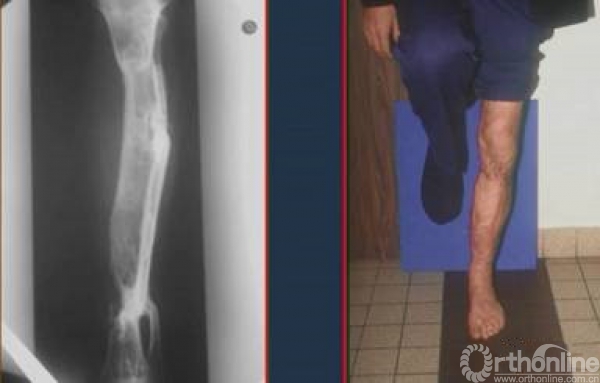

开放骨折,大段骨缺损。

采用皮瓣转移+骨水泥占位器

6周以后膜内成骨技术+大量RIA植骨

术后2年随访